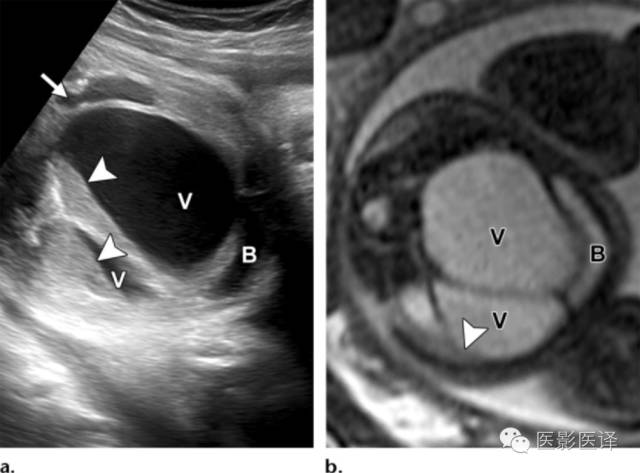

Nussbaum等最早将新生儿卵巢囊肿分为单纯性和复杂性。单纯性卵巢囊肿是圆的、无回声的、单房和薄壁的(图1)。它们更经常为单侧而非双侧、更经常为腹内而非盆腔内。单纯性囊肿内偶尔可见单个分隔(图2)。直径小于20mm的卵巢囊性结构被认为是成熟卵泡,为生理性而非病理性。直径大于20mm的囊肿则考虑为异常。“子囊”征描述的是囊内一个小的、圆形、无回声结构(图3)。既往报道认为这是卵巢囊肿的特征。【在一个23例囊性病变的研究中(包括新生儿、婴儿及儿童),11例发现子囊,占卵巢囊肿的82%(敏感度82%,特异度100%,阳性预测值100%),在其他囊性病变中未发现子囊,包括淋巴管瘤、肠重复畸形、肠囊肿、胎粪假性囊肿、阴道积液和脐尿管囊肿。】

图3:单纯性卵巢囊肿。(a)矢状位胎儿超声图像显示一个边界清楚薄壁腹内囊肿(箭头),其内可见一个子囊(箭)。囊肿位于膀胱(B)上方腹中线区。Uv=脐静脉。(b)同一病人轴位超声多普勒图像显示在薄壁卵巢囊肿中有两个子囊(箭头)